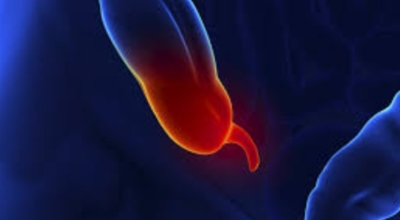

맹장은 소장의 말단부에서 대장으로 행하는 부위에 위치합니다. 주머니처럼 생겼고 소장에서 소화된 음식물이 이곳으로 넘어옵니다. 한편 충수는 10cm 정도 길이로 사람과 고등 영장류에게만 있고 이 충수의 입구가 막히거나 내용물을 맹장으로 보내지 못한다면 염증이 발생하는 것으로 보입니다. 이런 경우 대부분 수술적 절제가 필요한 급성 복통을 일으킵니다.